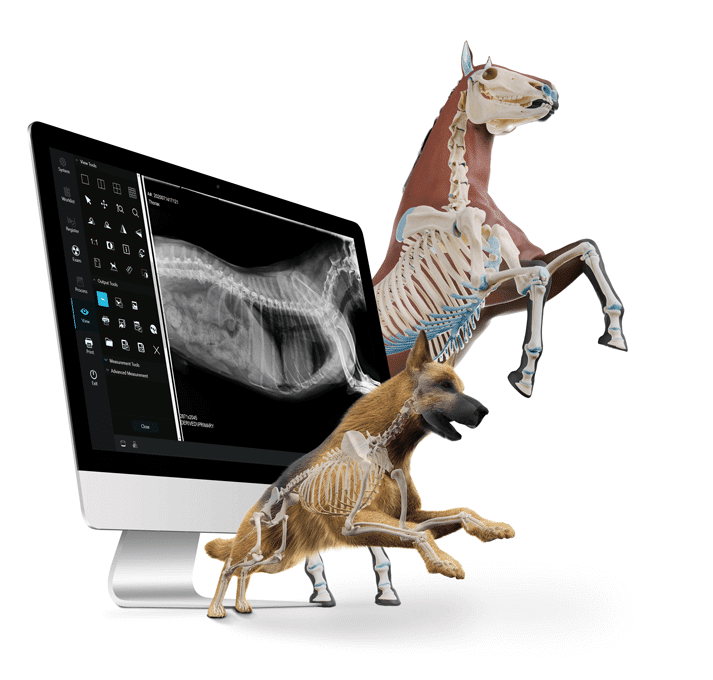

Enhance Your Productivity

With new digital veterinary X-ray technology from 1st Source, you can perform more high quality exams, faster than ever before. The combination of our new iQ Flex Pro paired with EVS W Series DR panels and IQ View veterinary software and our ultra-portable X-ray head enables a new era in digital radiography for imaging.

IQView veterinary software enhances the productivity of DR. The user-friendly interface combines with advanced image processing to quickly yield superior images. Available for use on desktops, laptops and tablets.

With IQ View veterinary X-ray software, productive imaging is just a click away. The intuitive user interface is easy to learn and easy to use. Patient positioning guides and animal specific protocols make imaging simple and quick. Calibrated for use with EVS W DR Panels Series to give you excellent image quality with lower dose for confident results.

Powerful Portable Imaging

The IQ Flex Pro* is a lightweight, battery powered solution that enables imaging flexibility in challenging environments. Carry the unit by the u-arm handle, or attach it to a tripod for assisted positioning. This efficient system produces high resolution images for rapid diagnosis.